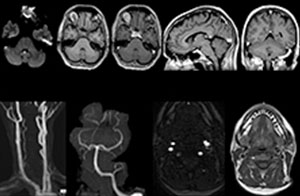

Clinical cases